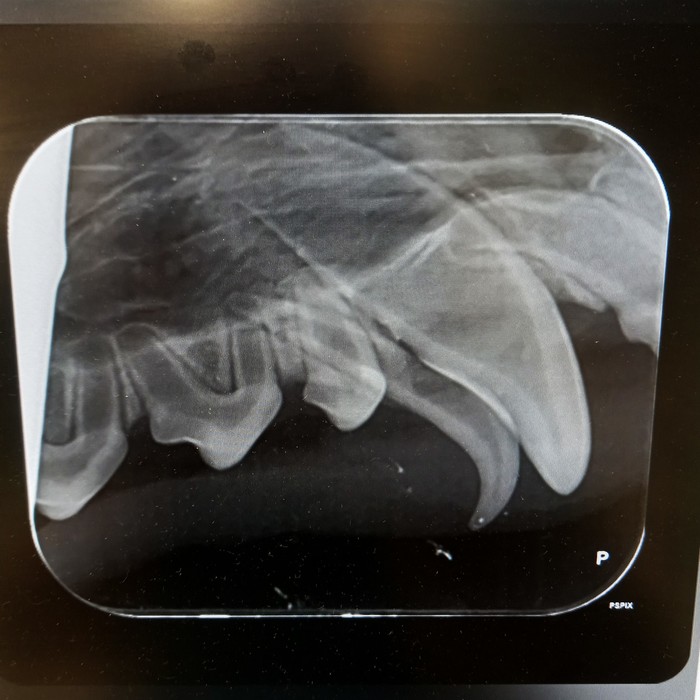

Rentgeny zubů se využívají na zobrazení hlubších vrstev zubů, kořenového systému zubů, posouzení parodontu a čelistních kostní.

Při rentgenologickém vyšetření posuzujeme následující struktury:

Korunka zubu: přítomnost a celistvost skloviny, šířka dentinu a jeho případné patologie, šířka dřeňové dutiny, celistvost zubu, při frakturách rozsah zlomenin, hledáme resorptivní léze, kazy, částečné/úplné fraktury, změny tvaru a celistvosti korunky

Krček zubu: celistvost krčku, resorptivní léze, kazy, fraktury

Kořen zubu: posouzení cementu na povrchu zubů, dentinu, dřeňové dutiny, fraktur kořenů, tvaru kořenů a jeho případných výběžků, přítomnosti tzv. pulpálních kamenů, osteoresorptivních lézí

Čelist: posouzení případných periapikálních reakcí, přítomnosti, úbytku či změny struktury alveolární kosti, přítomnost zlomenin čelisti či nádorového procesu, ne/přítomnost některých zubů

kořenové anomálie

kořeny mléčných zubů

periapikální absces

polámané kořeny v čelisti

vstřebávající se kořen špičáku

resorptivní léze